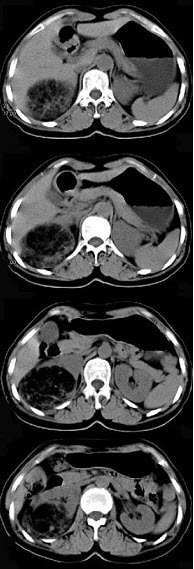

女,53岁,右侧轻度腰背酸痛,行CT检查,如图所示,可能的诊断为( )

A、右肾上腺髓样脂肪瘤

B、右肾上腺腺瘤

C、右肾上腺嗜铬细胞瘤

D、右腹膜后脂肪瘤

E、右肾血管平滑肌脂肪瘤